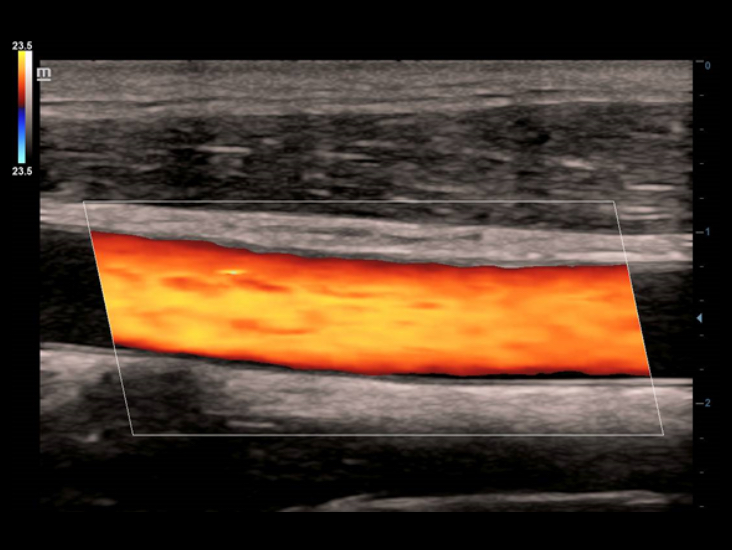

W porównaniu z tradycyjnymi g?owicami, w g?owicach ComboWave zastosowano nowy typ kompozytowego materia?u piezoelektrycznego, aby uzyska? znacz?c? optymalizacj? spektrum akustycznego i zredukowa? impedancj? akustyczn?. W po??czeniu z unikaln? technologi? 3T Mindray, g?owice liniowe ComboWave pozwol? uzyska? wysokiej jako?ci obrazowanie o doskona?ej rozdzielczo?ci i jednorodno?ci w badaniach tarczycy, piersi, naczyń krwiono?nych i innych.

Funkcja Smart Track zapewnia szybk? i inteligentn? optymalizacj? obrazów naczyń krwiono?nych zaledwie po jednym klikni?ciu. Umo?liwia optymalizacj? w trybach Dopplera Kolorowego, Power Dopplera i Dopplera spektralnego PW poprzez samodzieln? detekcj? naczynia i skrócenie czasu niektórych etapów badania. W ten sposób cykl czynno?ci podczas badania naczyń krwiono?nych zosta? uproszczony z jednoczesnym zachowaniem optymalnego obrazowania.